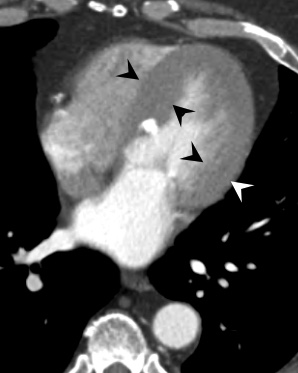

- Hypetrophie concentrique du VG (Ne se dilate que tardivement)

- Dilatation Post-Sténotique de l’Aorte ascendante

Insuffisance Aortique

- En lien avec une dilatation de la racine aortique (sur Atherosclerose ou Marfan) ou avec une calcification sévère des feuillets

- Dilatation ET Hypertrophie du VG